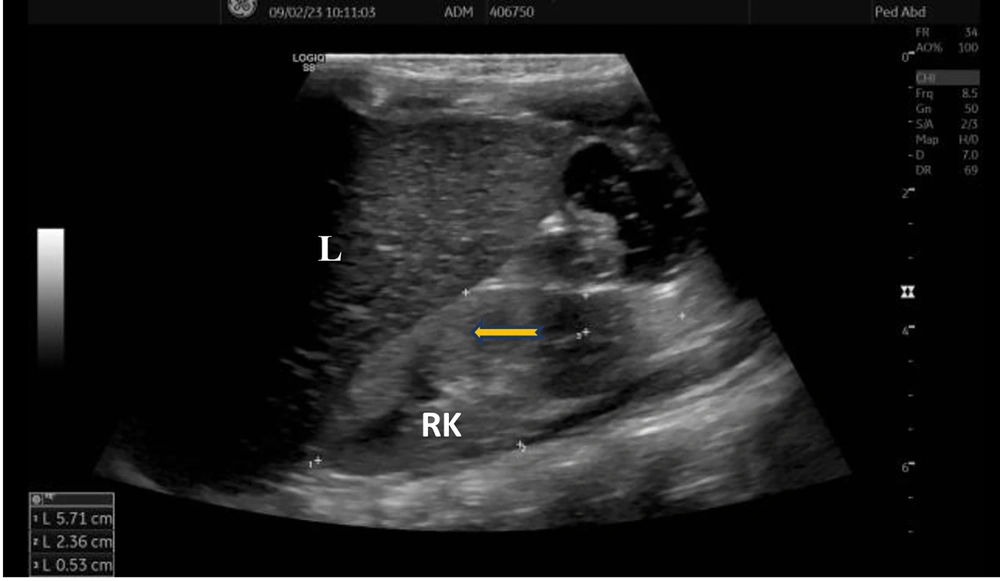

Laboratory investigations were as follows: Complete blood count was normal; routine urine analysis showed pH 9, density 1005, protein 1+, microscopy 4 - 6 leukocytes/area; serum urea was 89 mg/dL, creatinine 0.65 mg/dL, uric acid 13.4 mg/dL (normal: 2.6 - 6), sodium 136 mmol/L, potassium 2.4 mmol/L, chloride 80 mmol/L; blood gas analysis showed pH 7.65, bicarbonate 37 mmol/L, base excess +13 mmol/L; spot urine protein/creatinine ratio was 0.6 mg/mg. Rotavirus antigen was positive in stool, while stool and urine cultures were negative. She had hypokalemic hypochloremic metabolic alkalosis and proteinuria. Renal ultrasonography revealed increased echogenicity of the kidneys with loss of corticomedullary differentiation (Figure 1).

Increased renal echogenicity and loss of corticomedullary differentiation in the current case are also findings probably due to chronic hypovolemia. These findings may also be expected in acute or chronic renal failure and inflammation, as well as increased echogenicity may be a normal variant in underweight children. As proteinuria in our patient is not very high, we planned to observe and perform a renal biopsy and initiate angiotensin-converting enzyme inhibitors that have an antiproteinuric effect if proteinuria increases. Hypovolemia causes activation of the renin-angiotensin-aldosterone system, leading to glomerular hyperfiltration, so proteinuria occurs secondary to hypovolemia. We suggest that follow-up for proteinuria is important, and a decrease in proteinuria depends on fluid replacement. The aim and success of appropriate treatment with fluid and electrolyte replacement is the normalization of serum electrolytes, metabolic alkalosis, and proteinuria. Our patient is on sufficient water and 4 - 5 meq/kg/day KCl and 2 - 3 meq/kg/day NaCl replacement. Indomethacin was discontinued. Her growth and development have improved after 5 months (weight: < 3rd percentile, -2.32 SDS; height: 3rd - 10th percentile, -1.8 SDS; head circumference: 10th percentile, -1.32 SDS). Renal function tests normalized with episodes of rehydration. The long-term management plan should focus on monitoring renal functions, which may determine the overall outcome of the disease.